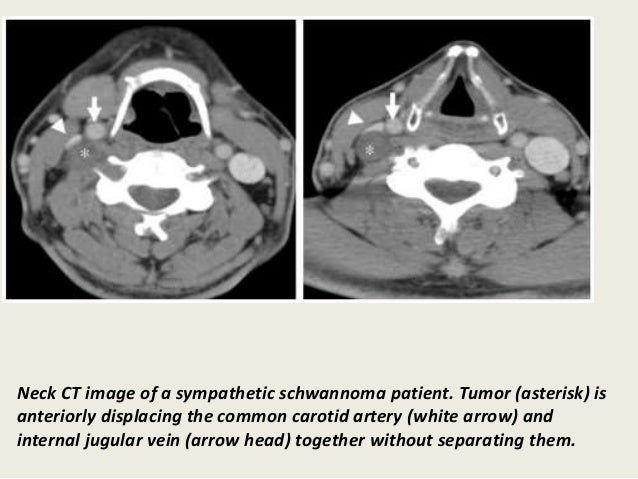

Presentation2, radiological imaging of neck schwannoma.

Presentation2, radiological imaging of neck schwannoma. from image.slidesharecdn.com